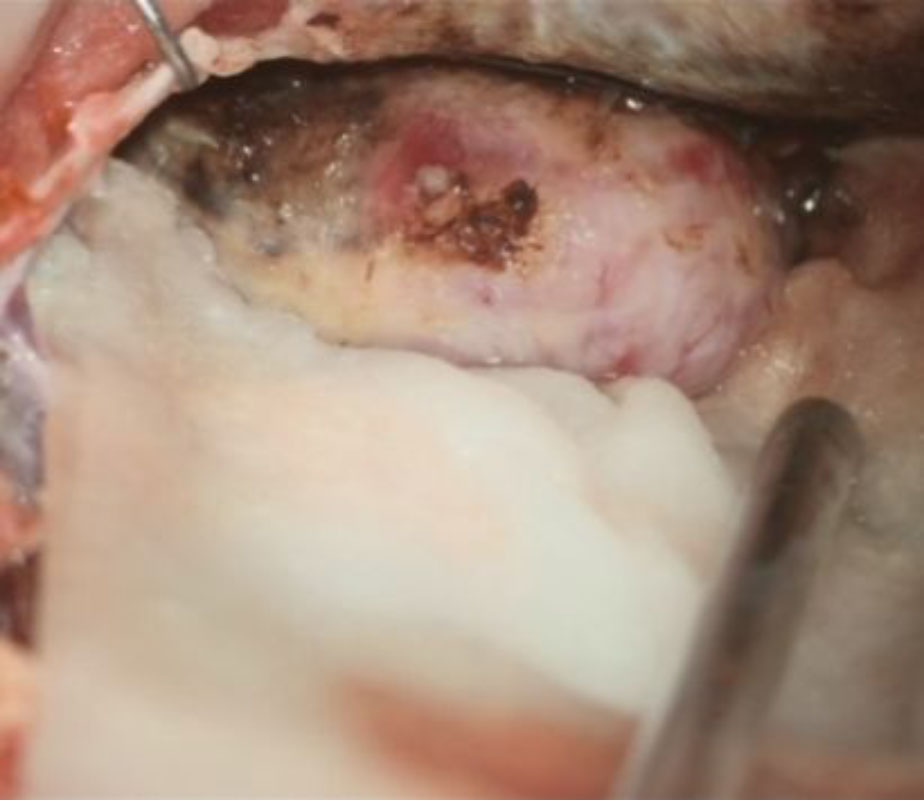

698

'25年11月

40代

右前頭葉腫瘍

頭蓋内腫瘍摘出術

No.’25_100 手術前1

No.’25_100 手術前2

No.’25_100 摘出 前

No.’25_100  摘出 中

No.’25_100 摘出 後